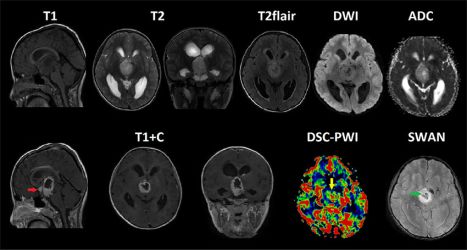

Представлен случай пилоциторной астроцитомы (grade 1 ВОЗ 2016), у девочки 3х лет, с жалобами на головные боли, тошноту, множественные эпизоды рвоты.

МРТ головного мозга и DSC-перфузия. Крупное отчетливо отграниченное образование, локализованное в гипоталамической области, с распространением в 3й желудочек (с признаками окклюзии последнего, вызывая бивентрикулярную гидроцефалию), межножковую и предмостовую цистерны. На постконтрастных T1-ВИ отмечается выраженное, относительно гомогенное контрастирование опухоли с зоной центрального некроза и наличием единичного узелка отсева в область хиазмы (красная стрелка), кроме того визуализируется сеть патологически расширенных сосудов и наличие микрокровоизлияний на ИП SWAN (зеленая стрелка). На перфузионных картах образование демонстрирует неоднородное повышение значений rCBV вокруг некроза (желтая стрелка) без видимого ограничения диффузии.

Высокие значения ADC могут быть использованы в качестве надежного фактора , указывающего на низкую клеточность пилоцитарных астроцитом. Повышение перфузионных показателей rCBV демонстрируют худшие диагностические критерии и являются не патогномоничными, поскольку пилоцитарные астроцитомы очень часто отражают высокие значения rCBV, таким образом имитируя опухоли высокой степени злокачественности. Вазогенный отек встречается редко - эта особенность так же является ценным ключом в постановке диагноза.